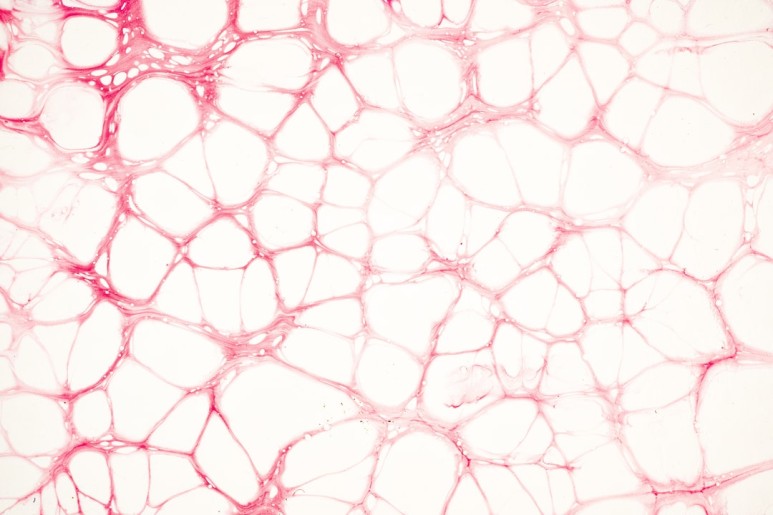

© flyd2069, 출처 Unsplash 소화작용을 보면 먼저 입에 들어간 음식은 위에서 반죽이 되고 십이지장을 지나 소장으로 갑니다. 소장의 역할은 영양소 흡수!이 흡수된 영양소는 소장에 미세하게 들어간 융모에서 흡수되어 혈관으로 들어가게 됩니다. 이 혈관에 들어간 영양소는 간 문맥을 통해서 심장, 심장에서 전신으로 뻗어나갑니다.

특히 탄수화물은 포도당으로, 과일을 통한 과당은 그대로 혈액으로 들어가 전신의 에너지원으로 사용됩니다. 그렇기 때문에 식후에 소화가 되어 혈중 당 수치가 자연스럽게 증가하는 것입니다.인슐린 저항성을 낮춰줍니다.식사 후, 소화 과정에서 혈중 당 수치가 올라갑니다. 이 때 인슐린도 그 후에 분비되어 이 당을 세포에 흡수해 주는 일이 됩니다. 지나치면 당을 지방세포에 저장합니다. 일정한 간격을 두고 당을 섭취하면 다행이지만, 종일 마시는 우리는 인슐린에 항상 목욕하는 상태에 이릅니다.그런데 식이섬유를 섭취하고 식사를 하면 흡수되는 당의 흡수가 늦어지고 인슐린 상승이 서서히 진행됩니다.

담즙산의 분비를 촉진시킵니다.식이섬유가 장관 내에서 담즙산과 결합하면 대변으로 배설되는 양이 증가하여 담즙산의 재흡수로 인한 장-간 순환 고리가 끊어집니다. 이 경우 간에서 새로 생성되는 담즙산의 양이 증가하며, 이때 그 원료인 콜레스테롤을 소모함으로써 혈중 콜레스테롤을 낮추는 효과를 볼 수 있습니다.